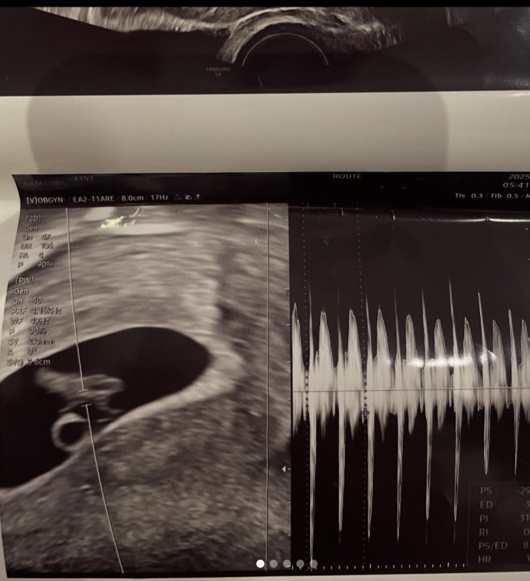

한편, 지난 2일 서민재는 자신의 SNS를 통해 “아빠 된 거 축하해”라는 글과 함께 초음파 사진, 남자친구의 SNS 계정, 얼굴이 드러난 사진, 재직 중인 회사와 학교 이름까지 공개하며 임신 사실을 밝혔다.